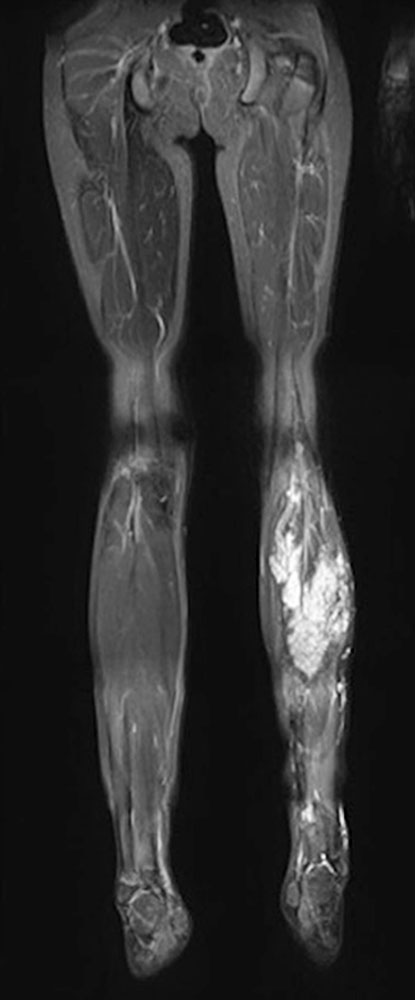

Particularly in fibro-adipose vascular anomaly (FAVA), contractures are to be expected owing to the regular constrictive connective tissue remodeling with shortening of the musculature. Most frequently, this relates to the calf muscles and a resulting pes equinus.

There is a loss of extensible muscle due to the remodeling of the existing musculature partly into connective tissue (fibrous connective tissue and fat) structures, partly interspersed with dysplastic venous vessels.

As the underlying bone grows, the surrounding altered muscle can no longer adapt to the new length ratios. This then leads to increasing contracture.

In these cases, removal of the FAVA including the affected muscle is recommended. This can be a very complex procedure if nerves and normal vessels are encased by the malformation in the knee area. However, to date this seems to be the only therapeutic approach to treat both the contracture and the other symptoms caused by FAVA.